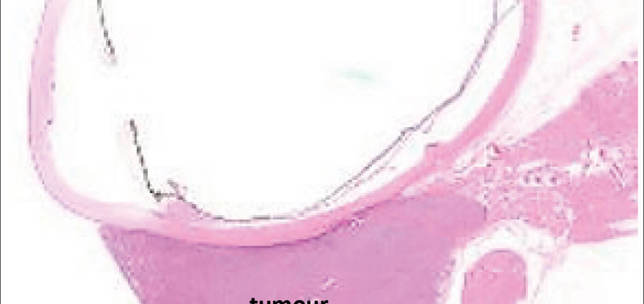

Pathology